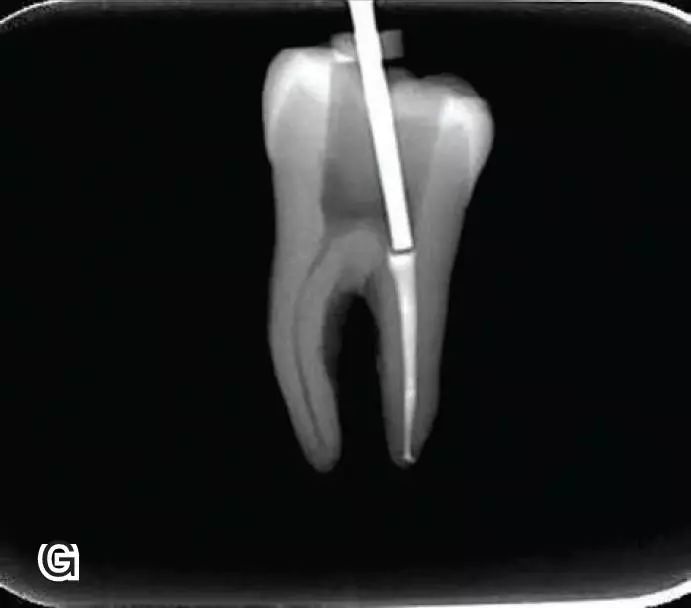

试尖

选择非标准牙胶尖(如0.04、0.06 锥度牙胶尖)作为主尖,型号一般与根管预备最大号的器械型号一致,能到达距根尖0.5~1 mm 处,主尖尖段与根管壁紧密接触。拍试尖X 线片进行确认。